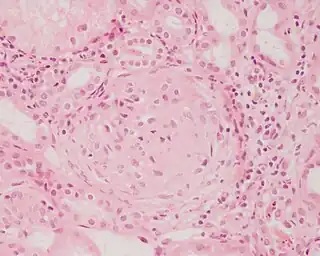

![]() Imagen histopatológica de una muestra de glomerulonefritis con semilunas obtenida de un paciente con glomerulonefritis rápidamente progresiva positiva para anticuerpos anti-MPO-ANCA. Tinción con hematoxilina y eosina. | ||

La glomerulonefritis rápidamente progresiva o extracapilar es un síndrome renal que si no se trata progresa con rapidez a una insuficiencia renal aguda y a la muerte del paciente en cuestión de meses. En el cincuenta por ciento de los casos esta glomerulonefritis se asocia con otra enfermedad de base, como por ejemplo el síndrome de Goodpasture, el lupus eritematoso sistémico o la granulomatosis de Wegener. Los casos restantes son idiopáticos, es decir, se ignora la causa de la aparición de la enfermedad. De todos modos, independientemente de la etiología principal, la glomerulonefritis rápidamente progresiva implica una serie de lesiones del glomérulo del riñón y la presencia de las típicas cicatrices con forma de semiluna en más del cincuenta por ciento de las unidades glomerulares.[1] En ocasiones, debido a esta característica histológica, la enfermedad recibe el nombre de glomerulonefritis semilunar.[1]

Pese a la gran variedad de enfermedades que causan glomerulonefritis rápidamente progresiva, todos los tipos se caracterizan por daño glomerular y formación de semilunas. El daño más grave y la ruptura de la membrana basal glomerular conducen a la pérdida de proteínas plasmáticas. De estas proteínas, se piensa que la fibrina es la que más contribuye a la formación de semilunas. Las células epiteliales que delimitan la cápsula de Bowman responden al estímulo proliferante de la fibrina. También puede haber infiltración de leucocitos como los monocitos y los macrófagos, los que también pueden proliferar bajo la influencia de la fibrina. Estas células proliferantes rodean al glomérulo y lo comprimen por lo que aparece la cicatriz con forma de semiluna que es visible con el microscopio en el material obtenido de una biopsia renal.[2]

Anatomía patológica

En la biopsia de estos pacientes se halla una importante proliferación de las células epiteliales de la cápsula de Bowman, con formación de semilunas en los glomérulos.[4] La biopsia renal confirma la presencia de una glomerulonefritis con semilunas epiteliales. Entre las características histopatológicas figura la infiltración del espacio urinario por células mononucleares asociada con la proliferación del epitelio parietal de la cápsula de Bowman o la proliferación extracapilar con formación de semilunas que pueden afectar del treinta al cien por ciento de los glomérulos. En estos se ve un engrosamiento de la cápsula de Bowman con formación de semilunas. También puede haber fibrosis parcial y sinequia del penacho glomerular a la cápsula.[4] Las semilunas, que pueden ser segmentarias o circunferenciales, ocupan todo el espacio de Bowman y ahogan el ovillo capilar, según el estado evolutivo pueden clasificarse en celulares, fibrocelulares o fibrosas y representan fases progresivas del mismo proceso.[4] En la glomerulonefritis rápidamente progresiva de tipo I hay positividad lineal sobre todo para IgG pero después también para C3. Dos tercios de las glomerulonefritis semilunares de este tipo corresponden al síndrome de Goodpasture y el otro tercio carece de manifestaciones pulmonares (síndrome de Goodpasture sin compromiso pulmonar). La lesión glomerular es similar en ambos grupos y se produce por un mecanismo inmunitario antimembrana basal glomerular. Como ya se dijo, el factor desencadenante es un defecto de un componente proteico de la cadena α3 del colágeno de tipo IV.[5] En la enfermedad de tipo II hay positividad granular o nodular o de ambas formas, difusa y global, debido a depósitos de complejos inmunes que con el microscopio electrónico se ven como depósitos densos. Este tipo por lo general corresponde a variedades de la glomerulonefritis aguda difusa, de la glomerulonefritis mesangiocapilar y, menos a menudo, de la enfermedad de Berger.[5]